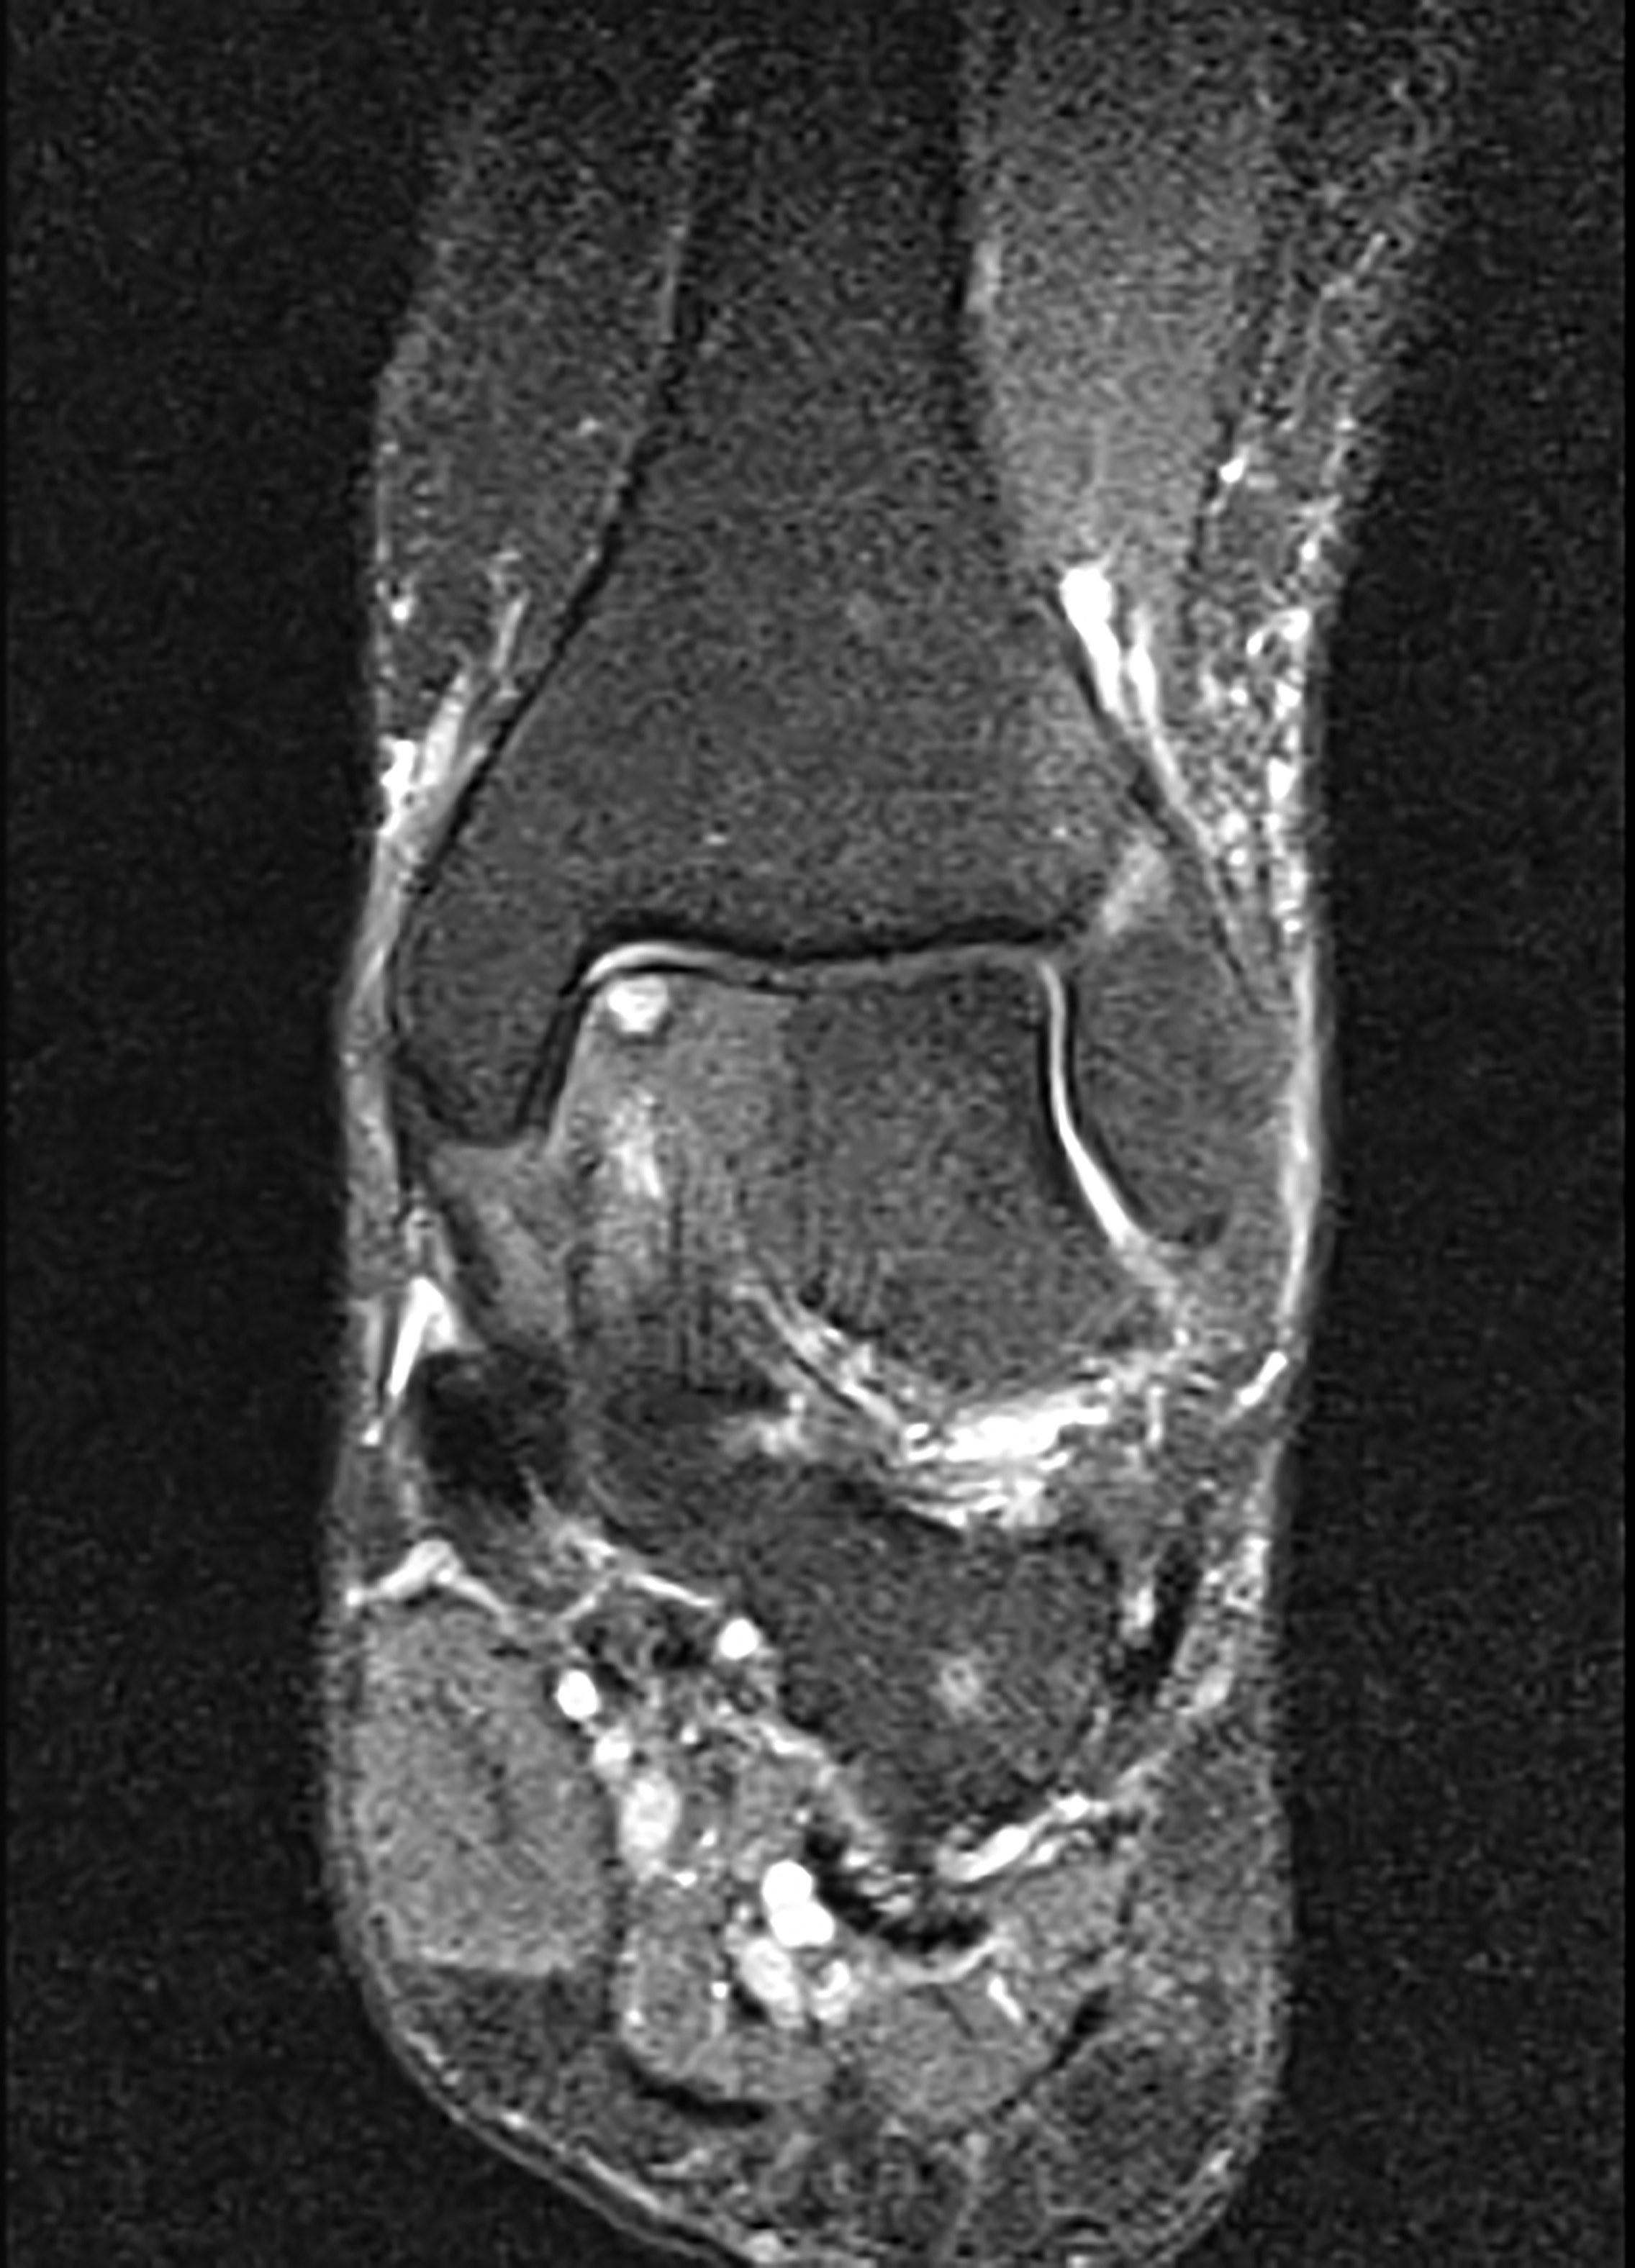

Sometimes they can be seen using plain X-rays but more often an MRI or CT scan is required to reveal the diagnosis and quantify the size of the defect .

Cylinders of cartilage and bone can also be taken from non-weight bearing areas of other joints (the knee most commonly) and implanted into the area of the defect (this is know as osteochondral grafting). This picture shows the talar defect prepared ready to accept the plug of bone and cartilage.

The recovery following this is similar to that following microfracture and the success rate broadly similar. It is normally held in reserve for those cases in whom microfracture does not work as it is more invasive , requiring one of the ankle bones to be surgically broken to gain adequate access to the joint(known as an osteotomy) as well as graft to be taken from a healthy joint (the knee) which can on occasion be painful afterward. Such a case is show below.